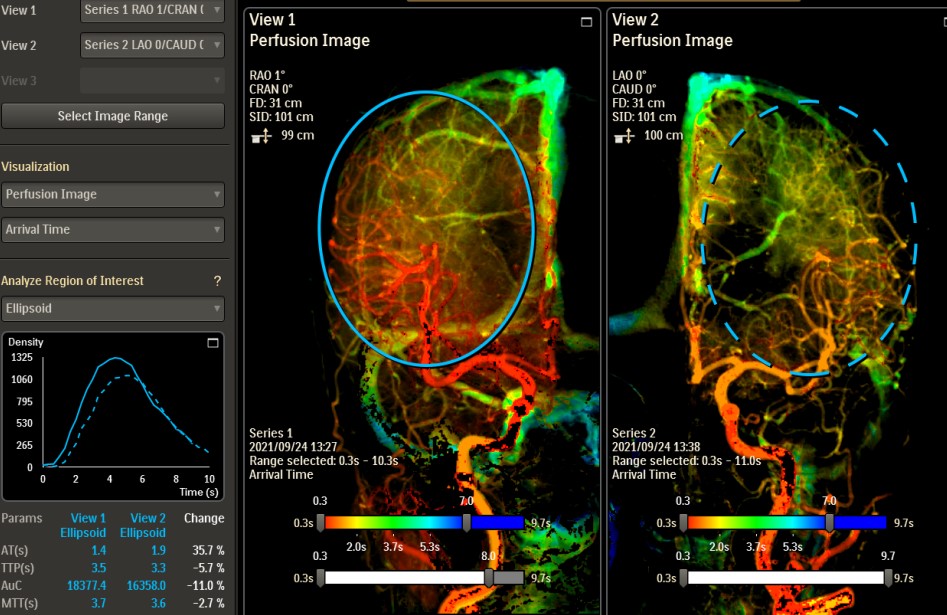

脳血管撮影

脳血管撮影では、頭頸部の血管をカテーテルから造影剤を流して撮影します。血管の走行を観察したり、必要に応じて血管の狭窄や閉塞を広げる治療や、動脈瘤をコイルで塞栓する治療、脳腫瘍などへの栄養血管に対して手術前の塞栓術を行ったりします。脳の血管をみる検査にはCTやMRIなどといった撮影もありますが、血管撮影装置での脳血管撮影ではそれらよりも細かい血管の状態まで観察することができます。

術前流速検査

脳血管の還流画像